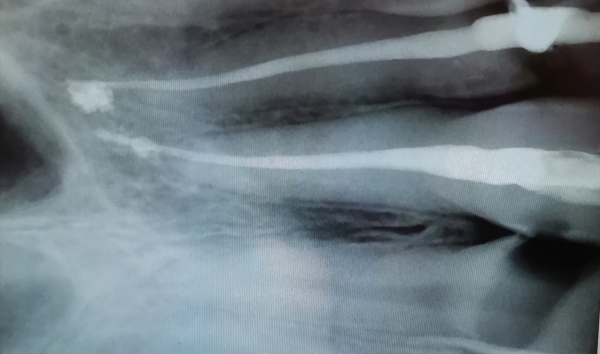

Мне при пломбировке каналов вывели гуттаперчу и силер за верхушку корня.

Меня беспокоили сильные боли в кости, а также больно было прикасаться к десне под крылом носа. Через месяц мне рас пломбировали 22-й зуб и извлекли всю гуттаперчу, которая была за верхушкой корня, а часть силера пришлось оставить, так как врач не смогла извлечь весь силер. После перелечивания побаливает кость над этим зубом, но уменьшилась боль при прикосновении к десне у проекции верхушек этих корней. При накусывании болит кость.

Сложно судить однозначно. За зубом следует наблюдать в динамике, через 1, 3 и 6 месяцев, по рентгеновскому снимку.